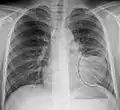

A chest X-ray showing a very prominent wedge-shape bacterial pneumonia in the right lung

The discovery of x-rays made it possible to determine the anatomic type of pneumonia without direct examination of the lungs at autopsy and led to the development of a radiological classification. Early investigators distinguished between typical lobar pneumonia and atypical (e.g. Chlamydophila) or viral pneumonia using the location, distribution, and appearance of the opacities they saw on chest x-rays. Certain x-ray findings can be used to help predict the course of illness, although it is not possible to clearly determine the microbiologic cause of a pneumonia with x-rays alone.